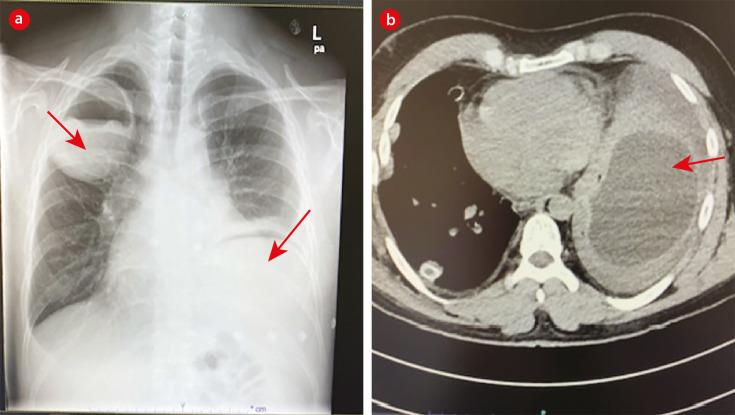

Over a 12-year period we saw nine cases of hydatid disease; two cases in females and seven cases in males. The median age of our patients was 31 years old. Four patients had pulmonary cysts, four had hepatic cysts, and one patient had pulmonary and hepatic cysts. The majority of patients were from the Ad Dakhiliyah governorate. Contact with animals was reported by three patients, denied by two, and unknown for four. Albendazole was prescribed to three patients with pulmonary cysts that subsequently ruptured reflecting the unfamiliarity of clinicians to best manage pulmonary hydatid cysts.

在12年期间,我们共诊治了9例包虫病病例;其中女性2例,男性7例。患者的中位年龄为31岁。4例患者有肺囊肿,4例有肝囊肿,1例患者既有肺囊肿又有肝囊肿。大多数患者来自达希利耶省。3例患者报告与动物有接触,2例否认,4例情况不明。3例肺囊肿患者使用了阿苯达唑,随后囊肿破裂,这反映出临床医生对肺包虫囊肿的最佳管理并不熟悉。